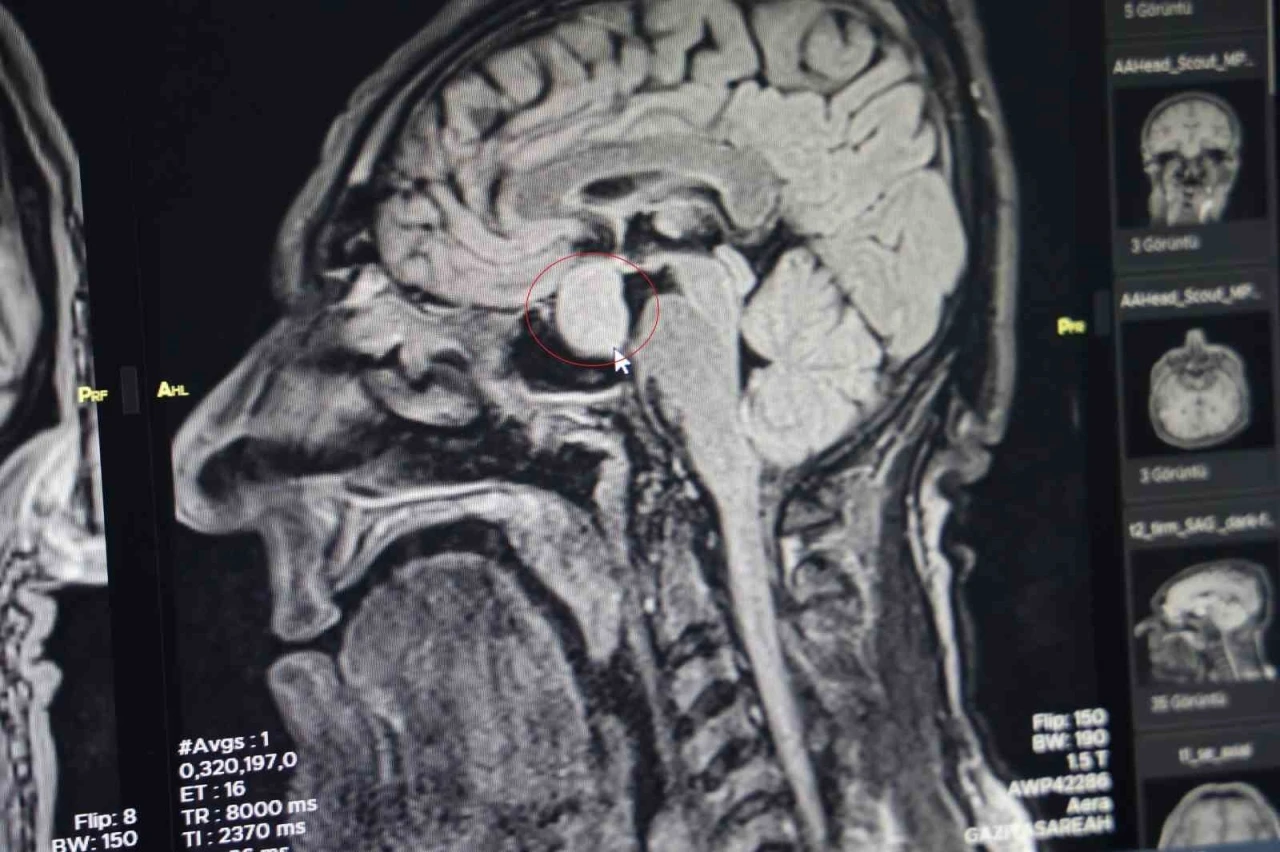

Diyarbakır Gazi Yaşargil Eğitim ve Araştırma Hastanesi, Beyin Cerrahi Bölümü'nde büyük bir başarıya imza atarak, ilk kez kapalı yöntemle beyindeki bir tümörü aldı. Bu yöntemle, 56 yaşındaki bir erkek hastanın beynindeki hipofiz tümörü başarılı bir şekilde çıkarıldı. Ameliyat, yaklaşık 2,5 saat sürdü ve komplikasyon yaşanmadan tamamlandı. Bu gelişme, bölge hastanesi olarak Gazi Yaşargil Eğitim ve Araştırma Hastanesi için bir ilki oluşturuyor.

Hastanın başvurusu, burun kökü ve dilinde kabalaşma, ses kalınlığı gibi şikayetlerle oldu. Yapılan tetkikler sonucunda, dış merkezlerde çekilen MR’larda hipofiz bölgesinde bir iyi huylu tümör tespit edildi. Bu nedenle hasta, hastaneye başvurdu. Beyin Cerrahi Bölümü’nde yapılan tetkiklerin ardından, hastanın büyüme hormonlarının yüksek olduğu belirlendi ve kapalı yöntemle hipofiz tümörü başarıyla alındı.